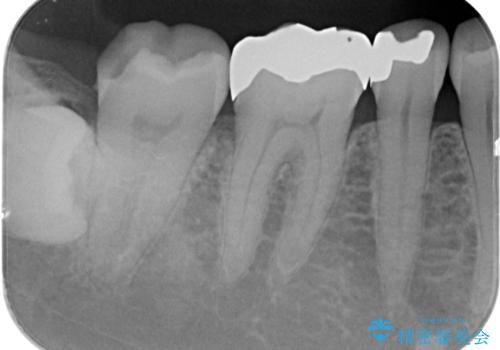

- 詰め物が外れたから作り直しをしたいとのことで来院されました。

外れた状態で日にちが経過していたため、まわりの歯ぐきが歯の上に乗っかっている状態です。

- 右下7 ゴールドインレー 77,000円費用は治療当時の料金となります